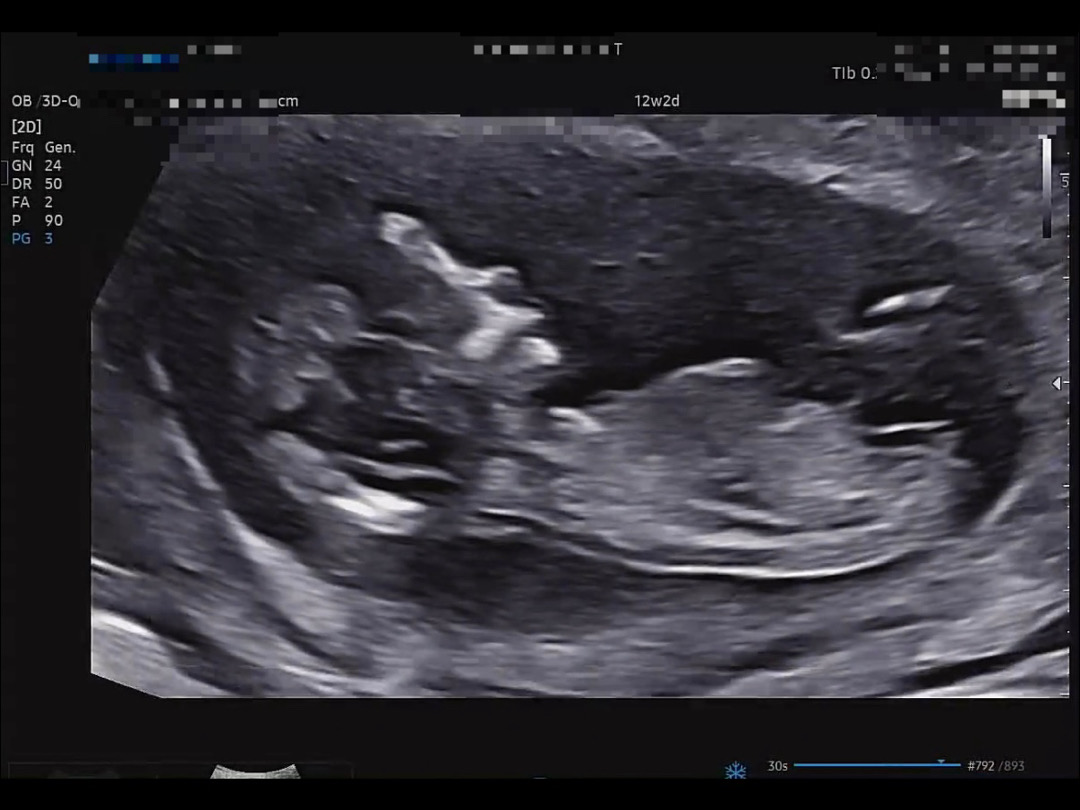

아들한표요!

각도법🥹

궁금해요 🥹🥹🥹❤️